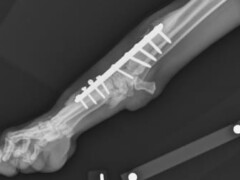

Radiographie numérique

Depuis 2024, nous avons équipé notre radiographe d’un capteur plan.

Mais qu’est qu’un capteur plan et pourquoi la Clinique Vétérinaire des Coquelicots a t’elle fait ce choix ?

Les capteurs plans présentent plusieurs avantages significatifs :

Réduction des doses de rayons X : l’un des principaux intérêts des capteurs plans est la diminution des doses de rayons X nécessaires pour obtenir une image de qualité. Cela est bénéfique pour la radioprotection des patients et permet également de prolonger la durée de vie des tubes à rayons X.

Qualité d’images : les capteurs plans permettent d’obtenir des images radiologiques numériques de haute qualité instantanément. Cette qualité d’image améliore le diagnostic en fournissant des informations précises qui étaient moins visibles avec les systèmes de numérisation indirecte (comme les cassettes classiques).

En résumé, les capteurs plans offrent une solution moderne et efficace pour la radiologie numérique, combinant qualité d’image, réduction des doses de rayons X, mobilité, et économies d’énergie.

Mobilité et portabilité : les capteurs plans sont plus pratiques et faciles à installer, notamment en radiographie mobile et vétérinaire. Leur conception sans fil et portable permet de les utiliser dans divers contextes, y compris les soins d’urgence et la chirurgie, où ils peuvent être facilement déplacés et positionnés.

Efficacité : ils permettent de réduire les temps d’acquisition et d’exposition pour les patients.

Économies d’énergie : les capteurs plans consomment moins d’énergie que les autres technologies.